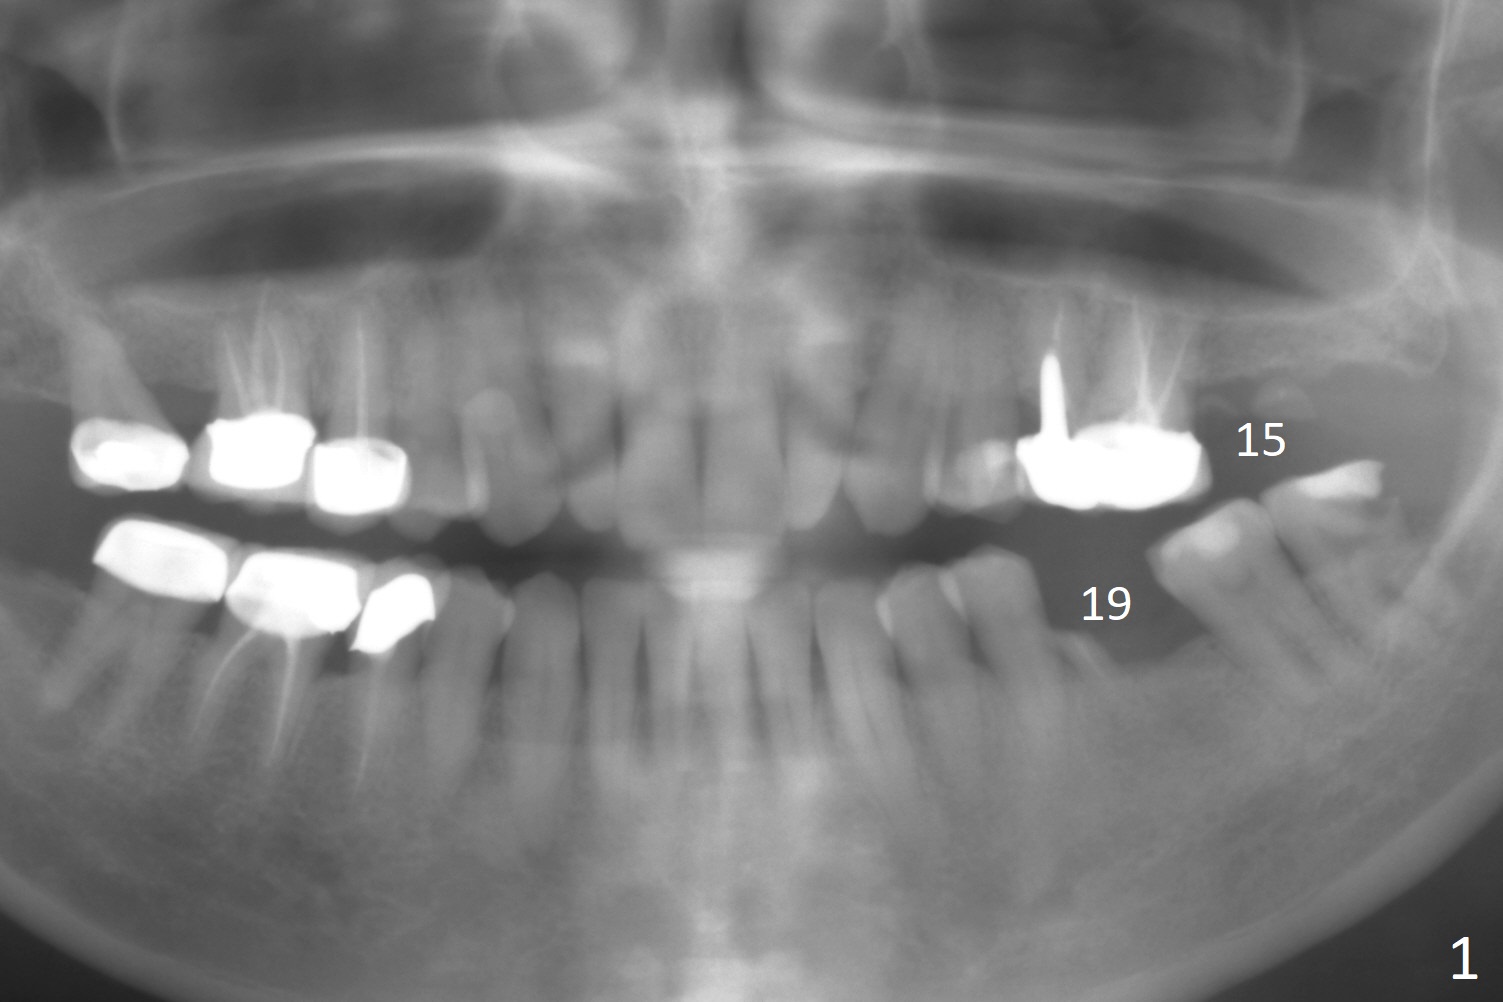

A 47-year-old woman has residual roots at #15 and 19 (Fig.1). Seven years earlier, the bone height is ~ 7 mm (Fig.2), as compared to ~5 mm now (Fig.3). It is apparent that the bone height decreases as the residual roots are expelled. An advantage is that the ridge is flat, easy to initiate osteotomy. Magic Sinus Lifter is to be used for sinus lift. The regular surgical kit should be also available. Proximators will be used to remove the residual roots. Magic Split may be used to initiate osteotomy.

It is also easy to initiate osteotomy at #19 after removal of the mesial residual root (Fig.3). A 5x11 mm IBS implant will be placed (first as compared to #15). After extraction, use Magic Split to increase osteotomy site, followed by Magic Expanders and/or Drills. Take preop photos of the site to show the possible narrow ridge.